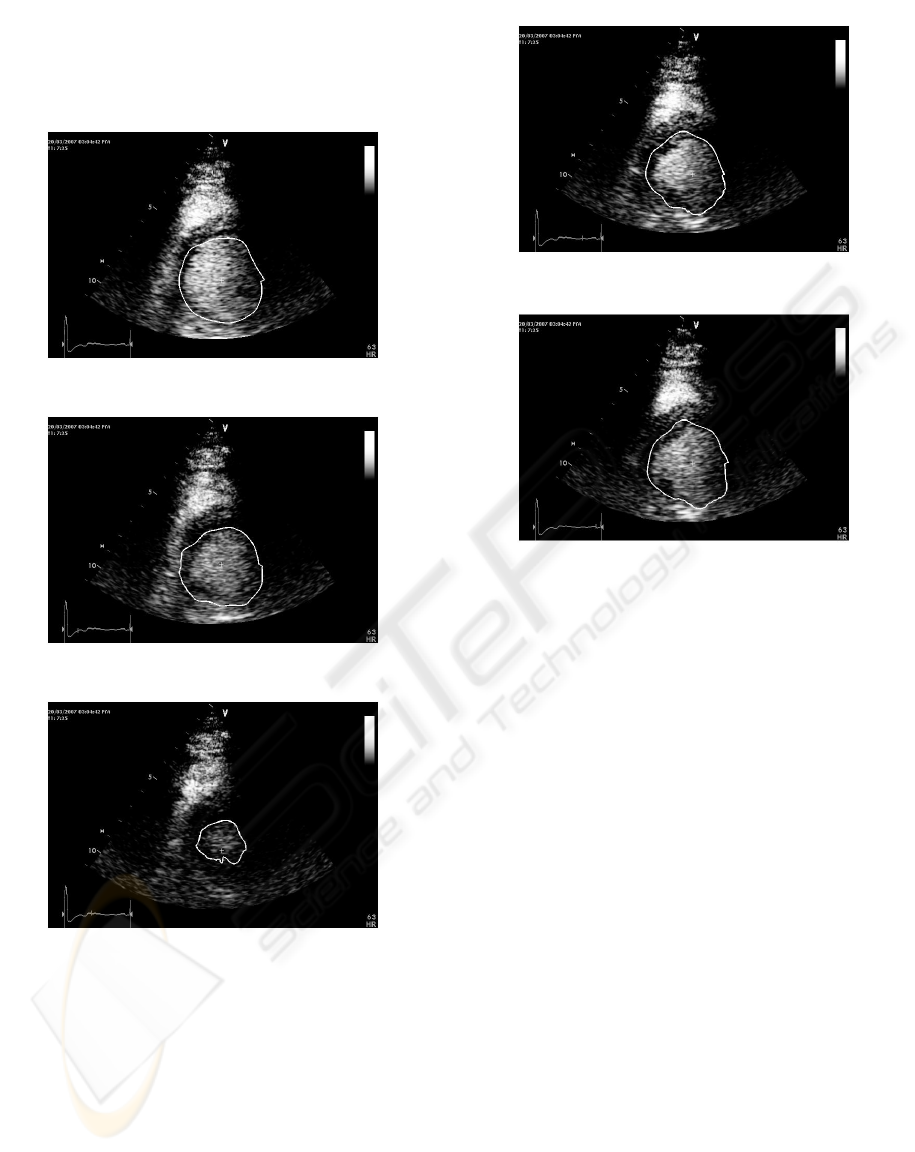

ENDOCARDIAL SEGMENTATION IN CONTRAST ECHOCARDIOGRAPHY VIDEO WITH DENSITY BASED

SPATIO-TEMPORAL CLUSTERING